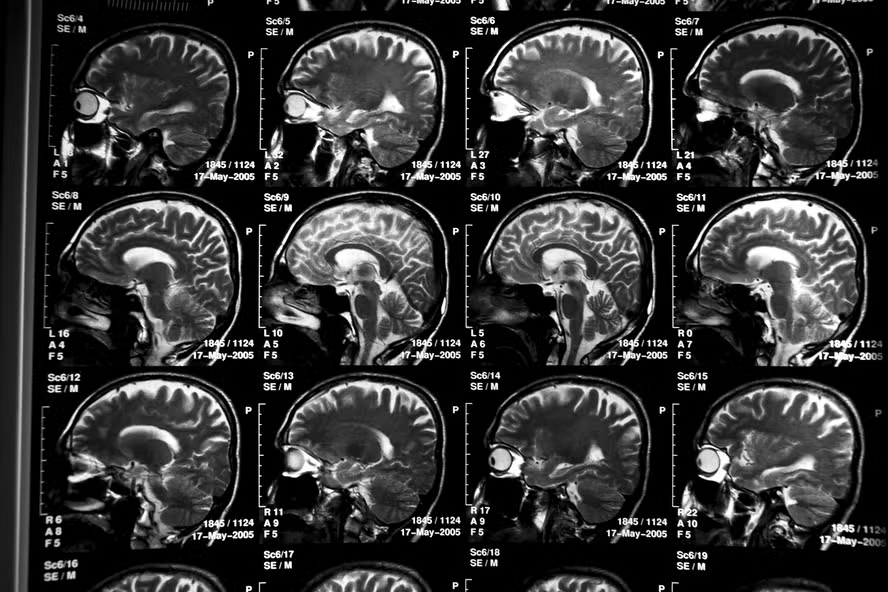

Os responsáveis explicam que, há cerca de uma década, mede-se a chamada “idade do cérebro”, um marcador que indica o quão velho o órgão aparenta a partir de exames de ressonância magnética. Um cérebro mais envelhecido do que a idade real do indivíduo é ligado a um risco maior de declínio cognitivo.

Na pesquisa, os cientistas analisaram exames de 41.708 adultos, que participaram do UK Biobank, um grande banco de dados de saúde britânico. A diferença é que eles dividiram o cérebro em 148 regiões e, em seguida, mediram separadamente o envelhecimento acelerado ou retardado em cada uma delas.